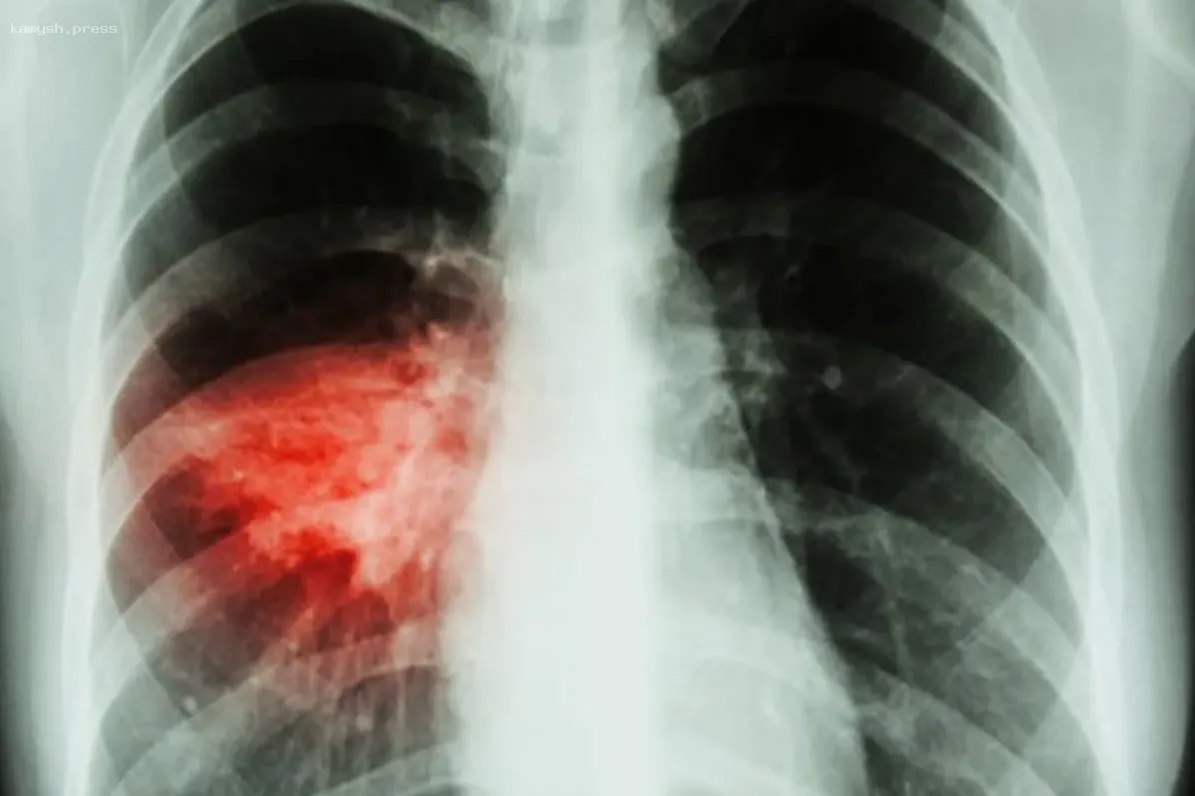

Последние две недели в Тюменской области наблюдается тревожная тенденция - резкий рост случаев внебольничной пневмонии. По данным областного управления Роспотребнадзора, этот показатель достиг 63 на 100 тыс. населения. Ситуация осложняется сезонным ростом заболеваемости ОРВИ и коронавирусом, что, по мнению специалистов, связано с началом учебного года и формированием детских и трудовых коллективов.